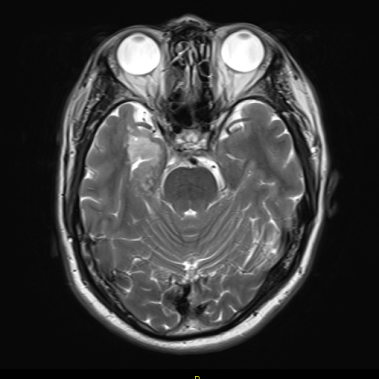

| Info: | 突发意识不清,手脚僵硬11天,患者于2022-03-18无明显诱因下意识不清,手脚僵硬,牙关紧闭,口角向左歪斜,10余分钟后自行缓解,事后不能回忆,当地头颅MRI示右侧颞叶-海马区占位,考虑低级别胶质瘤。遂于2022-03-29入我院拟手术治疗。既往史、个人史、家族史均无特殊。 手术所见:肿瘤组织位于深部,呈暗灰色,质地稍硬,与周围脑组织境界不清,血供一般。 |

| Sample: | 右侧颞叶-海马区占位 |

| Grossly: | 灰白灰红脑组织一堆,大小合计4*3.2*1.5cm,大部分为正常组织,可见局灶灰白质嫩区,大小约1.5*1.5*0.7cm。 |